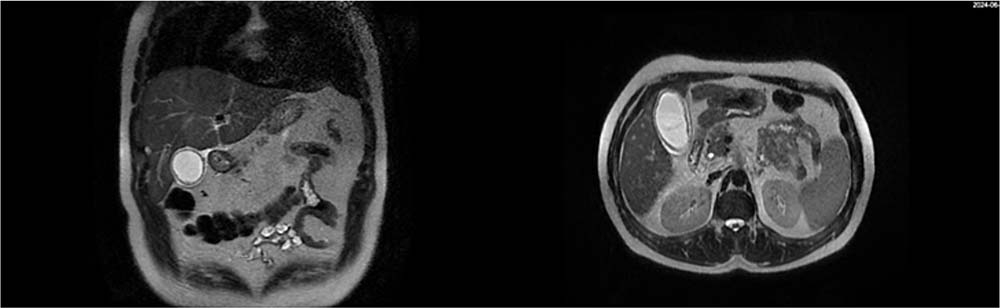

图2 MRI显示胆囊壁增厚、胆囊周围积液,胆总管正常